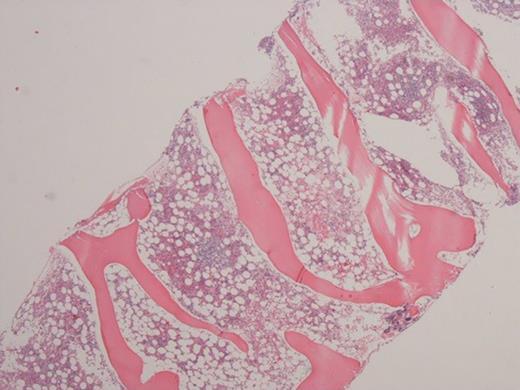

Immune checkpoint inhibitors (ICIs), including anti-cytotoxic T-lymphocyte antigen 4 (anti-CTLA-4) and anti-programmed death receptor-1/ligand-1 (anti-PD-1/anti-PD-L1) caused a breakthrough in oncology and significantly improved therapeutic outcomes in cancer patients. ICIs generate a specific reaction in T cells, directed against antigens on cancer cells, leading to their damage and death. Through similar or the same antigens, activated lymphocytes may also have a cytotoxic effect on healthy cells, causing development of specific adverse effects - so-called immune-related adverse events (irAEs). We present the case report of a 56 year old patient with disseminated melanoma. During treatment with immunotherapy (anti PD-1), neutropenic fever and pancytopenia occurred. Trepanobiopsy of the bone marrow was performed to determine the cause of pancytopenia. Histopathological assessment of bone marrow combined with immunophenotype investigations may explain the cause of hematological disorders occurring in the course of treatment with ICIs, and support the choice of an appropriate treatment, directly translated into positive outcomes.

免疫检查点抑制剂(ICIs),包括抗细胞毒性T淋巴细胞抗原4(抗CTLA-4)和抗程序性死亡受体-1/配体-1(抗PD-1/抗PD-L1),在肿瘤学领域带来了突破,并显著改善了癌症患者的治疗效果。ICIs在T细胞中引发针对癌细胞上抗原的特异性反应,导致癌细胞受损和死亡。通过相似或相同的抗原,活化的淋巴细胞也可能对健康细胞产生细胞毒性作用,从而引发特定的不良反应——即所谓的免疫相关不良事件(irAEs)。我们报告了一例56岁播散性黑色素瘤患者的病例。在接受免疫治疗(抗PD-1)期间,出现了中性粒细胞减少性发热和全血细胞减少。进行了骨髓环钻活检以确定全血细胞减少的原因。骨髓组织病理学评估结合免疫表型研究,可能解释ICIs治疗过程中发生血液系统疾病的原因,并支持选择合适的治疗方法,直接转化为积极的治疗结果。